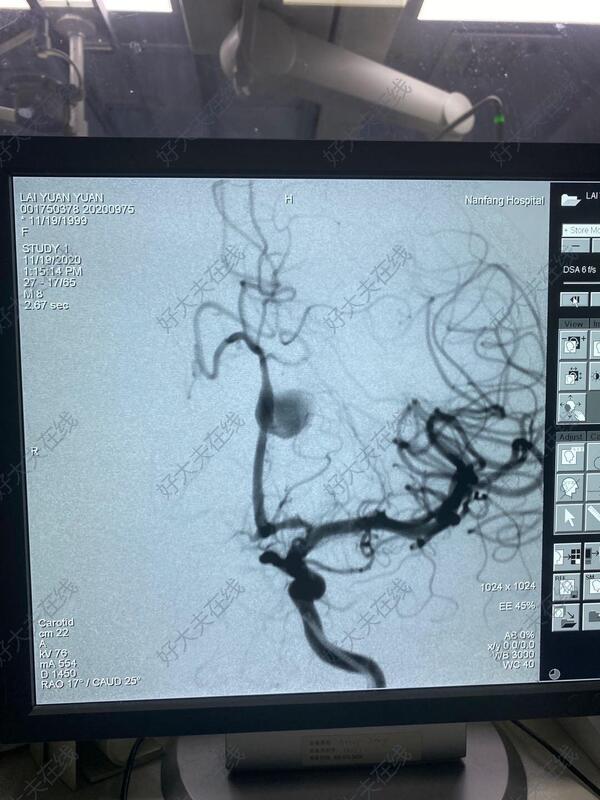

治疗前

21岁年轻女性,头痛检查发现左侧大脑前动脉A2段大型动脉瘤,植入密网支架重建血流,以达到修复血管,治愈动脉瘤的目的